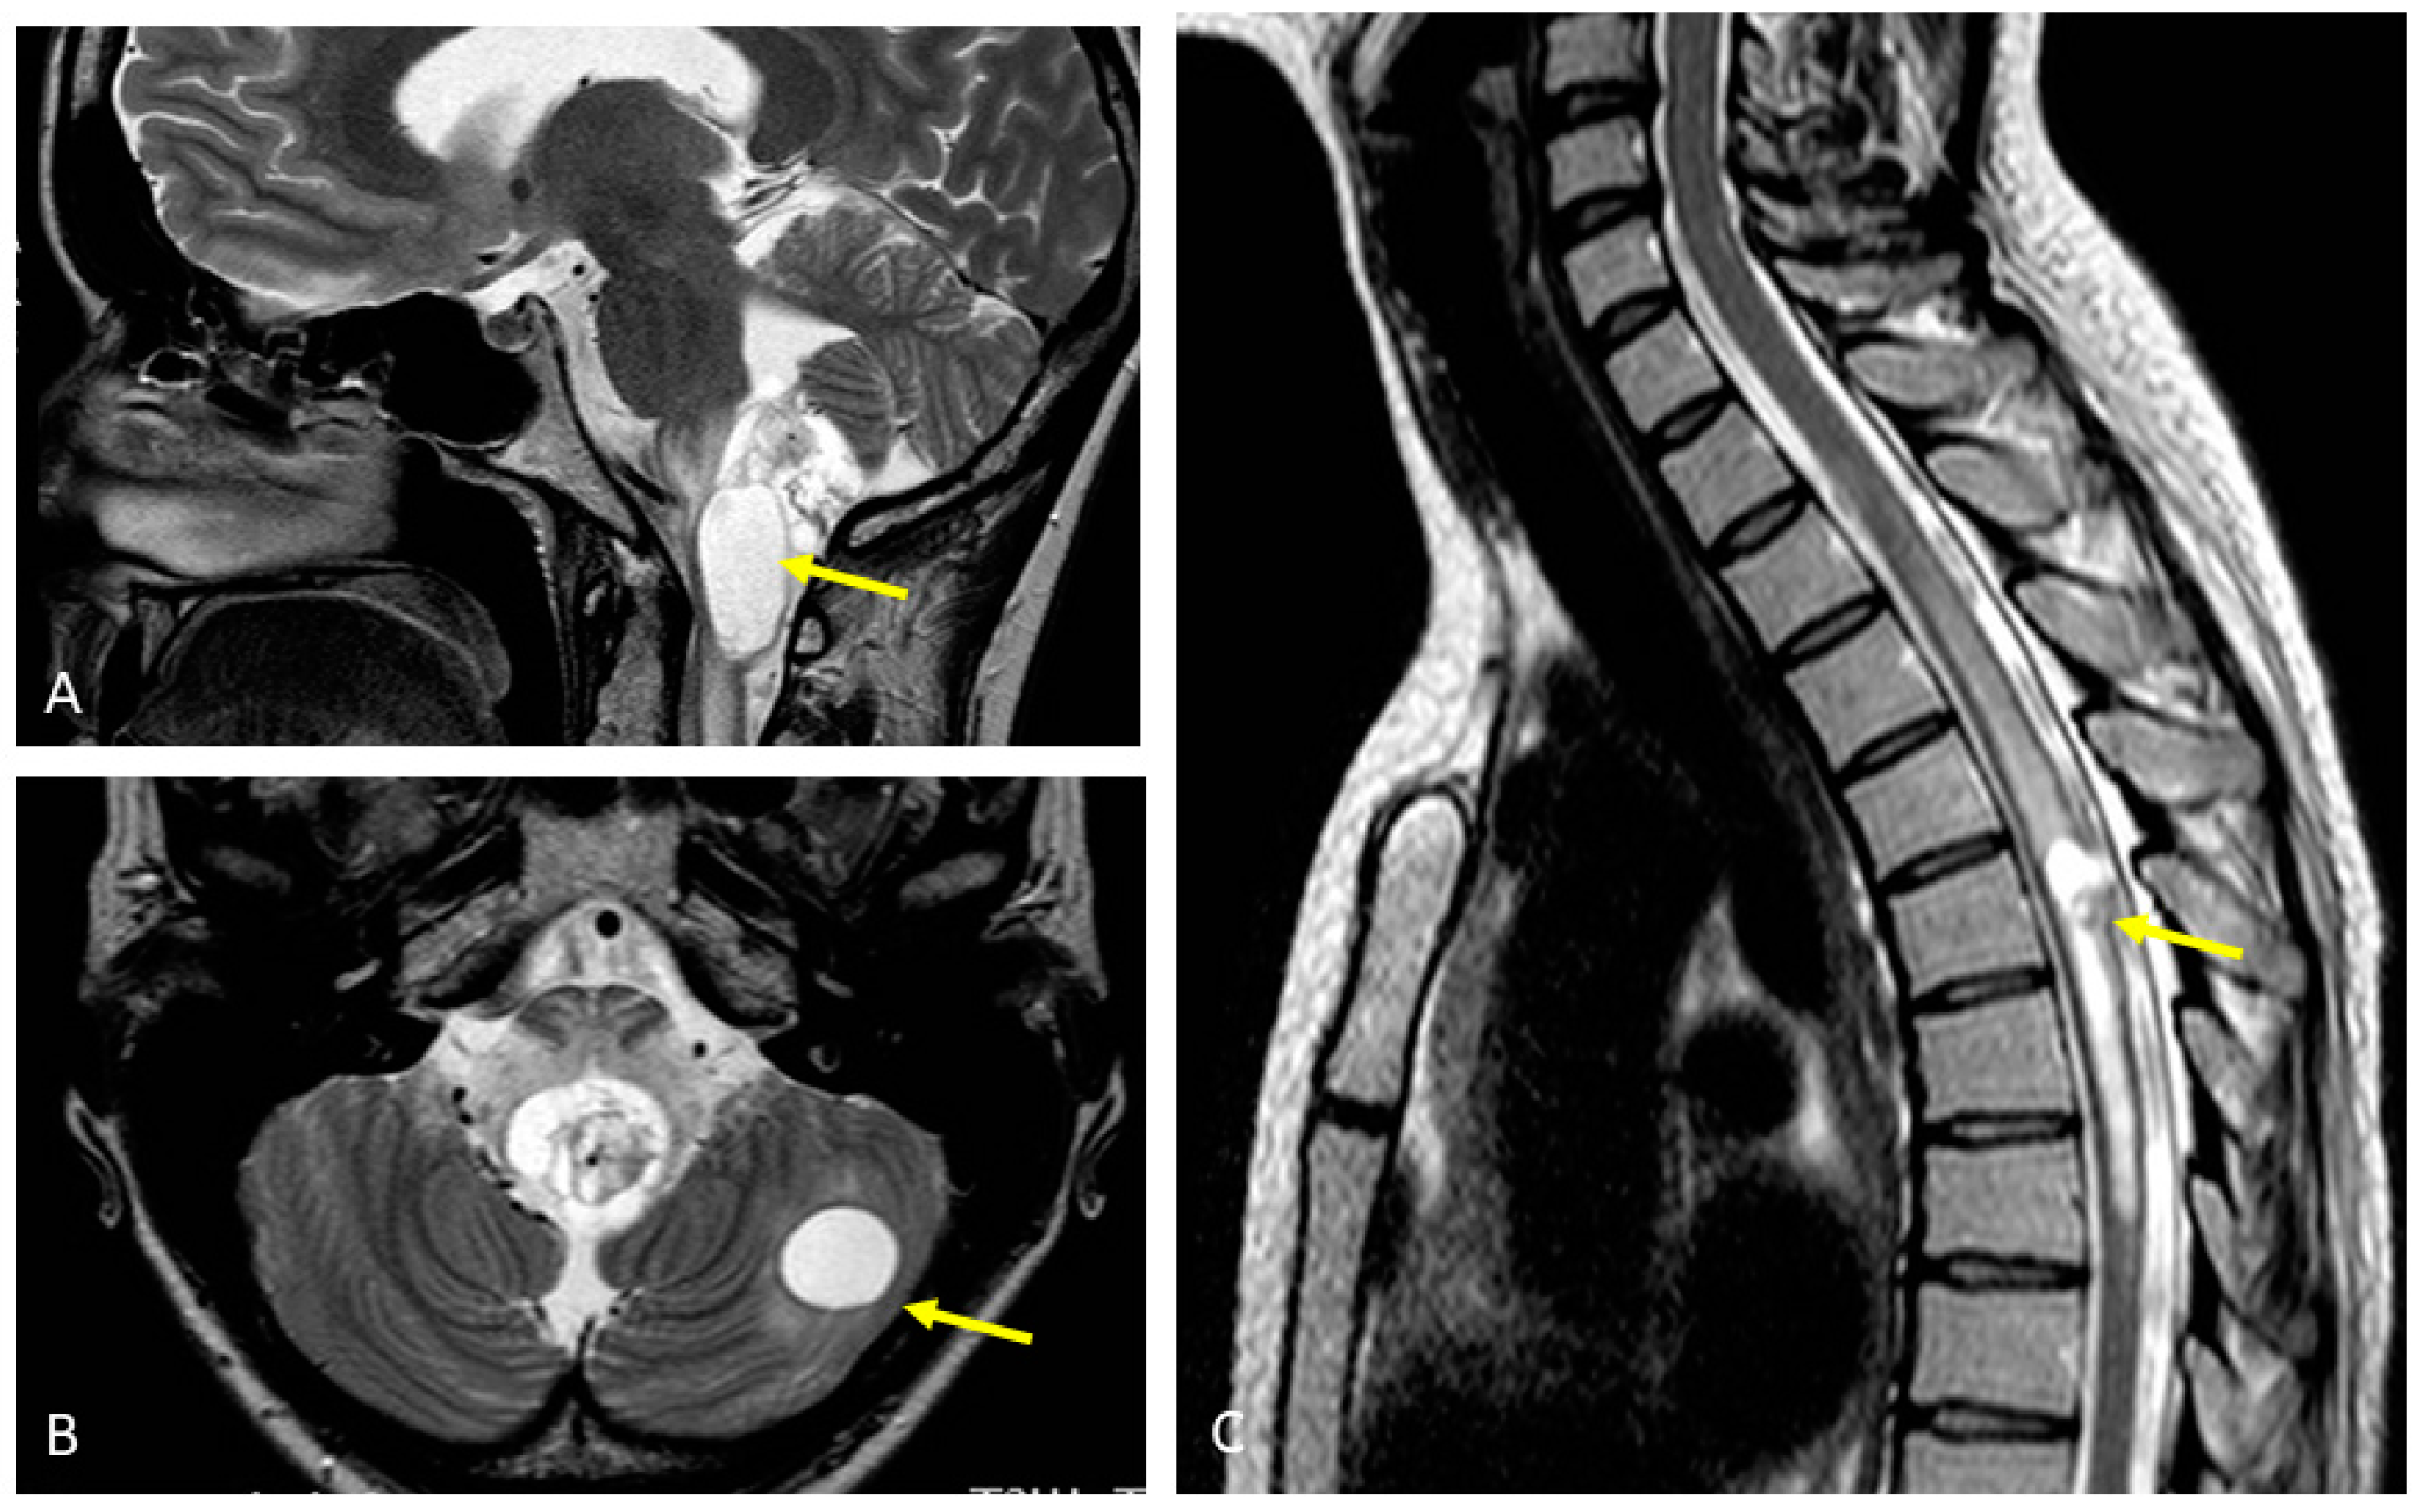

The patient underwent extensive diagnostics. Magnetic resonance imaging (MRI) of the head showed a 45 × 20 mm large, partly cystic space-occupying lesion at the base of the 4th ventricle, pressing the brainstem and upper spinal cord (Figure 4A). Two similar lesions were present in the left cerebellar hemisphere (Figure 4B). There were several similar lesions evident in the spinal cord MRI, the largest one being located at the C2 level, and the others at the C5-C6, Th1-Th3, Th5, and Th10 levels (Figure 4C). All lesions were consistent with hemangioblastomas.

Figure 4.

MRI imaging showing CNS lesions of the patient consistent with hemangioblastomas (yellow arrows): (A) Lesion pressing the brainstem and upper spinal cord; (B) Cerebellar lesion; (C) Spinal cord lesion.